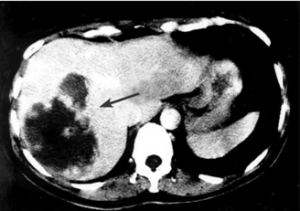

| תצלום 30.10: שאת בכבד הנראית ב- CT. מימין HCC הבולטת על פני הכבד. משמאל פגם מילוי בכבד כביטוי לשאת בכבד (החץ מצביע על השאת). | |

|---|---|